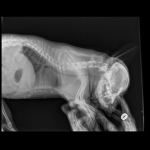

Французский бульдог,6 лет.Стала плохо ходить,что- то с позвоночником.Врачи не могут поставить диагноз.Есть снимки.Помогите!

Можете приложите к следующему комментарию снимки, я их посмотрю. Хотя, если бы на них были изменения, то Ваши врачи их бы увидели.

Снимки хорошие, качественные, но совершенно не информативные. На этих пленках патология не определяется. Но здесь нет снимка, который нужен обязательно - поясничный отдел позвоночника в прямой проекции (такой, как 3-й, но только не шея, а поясница).

Нет,наоборот.Собака сначала стала немного наклонять голову вправо.Когда были на консультации у окулиста,то он обратил внимание на это ,сказал,что есть какие-то изменения в области шеи.Я отсутствовала дома 2 недели.Приехала,собаку вообще не узнала.Крен головы вправо стал еще сильнее,передние ноги как-то ослабли.Она идет,может споткнуться,упасть.Сходили,сделали рентген.снимок.Поставили диагноз:атланто-аксиальная нестабильность шейного отдела,спондилоартроз. Проколола 5 дней:актовегин,папаверин,комбилипн,мидокалм,дексаметазон. Пока делала уколы и еще дней 5 после этого собаке стало легче,а потом опять вернулись к тому, что было.На консультации врач сказал,что дальше просто колоть преднизалон. Я уехала к другому врачу,тот сделал снимки,которые я Вам отослала.Сказал, что диагноз не подтверждает,на пальцах показал, что со спинным мозгом все нормально.С помощью какой-то процедуры (бумаги на работе)обнаружил перфорацию барабанной перепонки.Выписал лечение:цефтриаксон,циклоферон,цебролизин(колола 2 дня,стало хуже),комбилипен.В уши-изотик.Сказал,что может быть у собаки был инсульт.Собаке от лечения хуже.Вот такие дела.